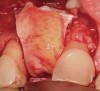

Figure 14  (Case 2) Failed implant at surgical exposure.

Figure 14

Figure 15  (Case 2) Defect after implant removal.

Figure 15

Figure 16  (Case 2) Defect grafted with mineralized freeze-dried bone allograft.

Figure 16